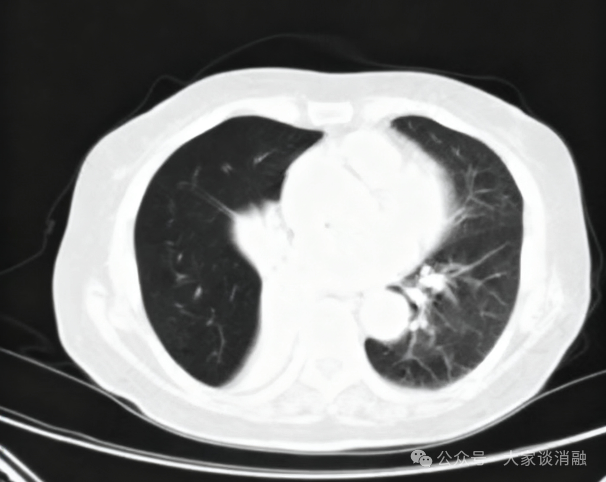

夏奶奶近两年来一直被间断的胸闷、气短、咳嗽、咳痰困扰。半月前,她的病情急剧加重,出现了痰中带血的症状,家人紧急送至东院区。呼吸与危重症医学科阎杰副主任医师接诊后,立即为夏奶奶进行胸部增强CT检查。结果提示“右肺门增大,右肺主支气管内结节状软组织密度灶,右肺下叶不张”,高度怀疑恶性肿瘤。

*患者CT检查

在与家属全面沟通并取得同意后,11月17日,尚东主任在王丽主管护师、李雪护师的密切配合下,成功为夏奶奶实施了PTS化学消融术。术中,尚东主任通过支气管镜将药物甲苯磺酰胺注射液(PTS)精准注射到肿瘤内部,术中即可见肿瘤组织迅速回缩、结构变得疏松,气管镜得以成功探入此前被堵塞的右中间支气管,手术过程顺利。术后3天,复查气管镜,原本狭窄的管腔已显著好转,右肺下叶及右中叶支气管开口清晰可见,夏奶奶的呼吸变得顺畅,气短症状极大缓解,未再出现咯血,目前已顺利出院。